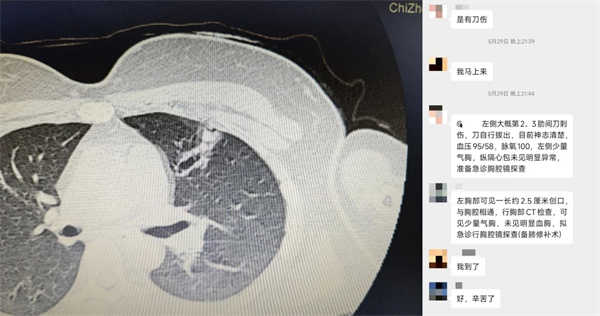

患者因左上肺意外刀刺伤,被紧急送至我院急诊科。急诊科与胸外科医师迅速完成初步评估,初步诊断为开放性创伤性血气胸,需紧急手术。医院立即启动创伤救治绿色通道。院领导高度重视,医务科立即协调资源,创伤外科等相关科室第一时间介入会诊,胸外科主任曹晓敬迅速组建救治小组,完善关键检查,精准评估伤情,为手术争取黄金时间。

时间紧迫,患者被快速转运至手术室。在麻醉科与手术室护理团队的密切配合下,曹晓敬主任带领甘结芳、许涛、高东明等骨干医师,在高清影像引导下,成功实施胸腔镜探查、左肺上叶前段部分切除、肺裂伤修补、胸膜粘连松解、胸壁创口清创缝合术。微创切口显著减小了手术创伤,精细操作有效保障了患者的肺功能。

术后,胸外科团队实施精细化护理,密切监测胸腔闭式引流情况,确保引流通畅。术后第三天复查胸部CT显示,胸腔恢复良好,积气积液吸收满意,术区愈合符合预期。经评估达到拔管指征,患者顺利拔除胸引管,康复出院。